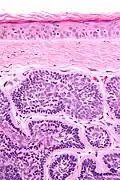

Dermal cylindromas are:

- Dermal lesions consisting of nests of cells that are surrounded by hyaline (i.e., glassy, eosinophilic, acellular) material and have:

- Hyperchromatic nuclei that may palisade (columnar nuclei arranged around the periphery of the cell nests with their short axis tangential to the nest periphery), and

- Cells with lighter staining ovoid nuclei at their centre.

They lack of a significant number of lymphocytes; this differentiates them from spiradenomas.

Micrograph of a dermal cylindroma in H&E stain. -